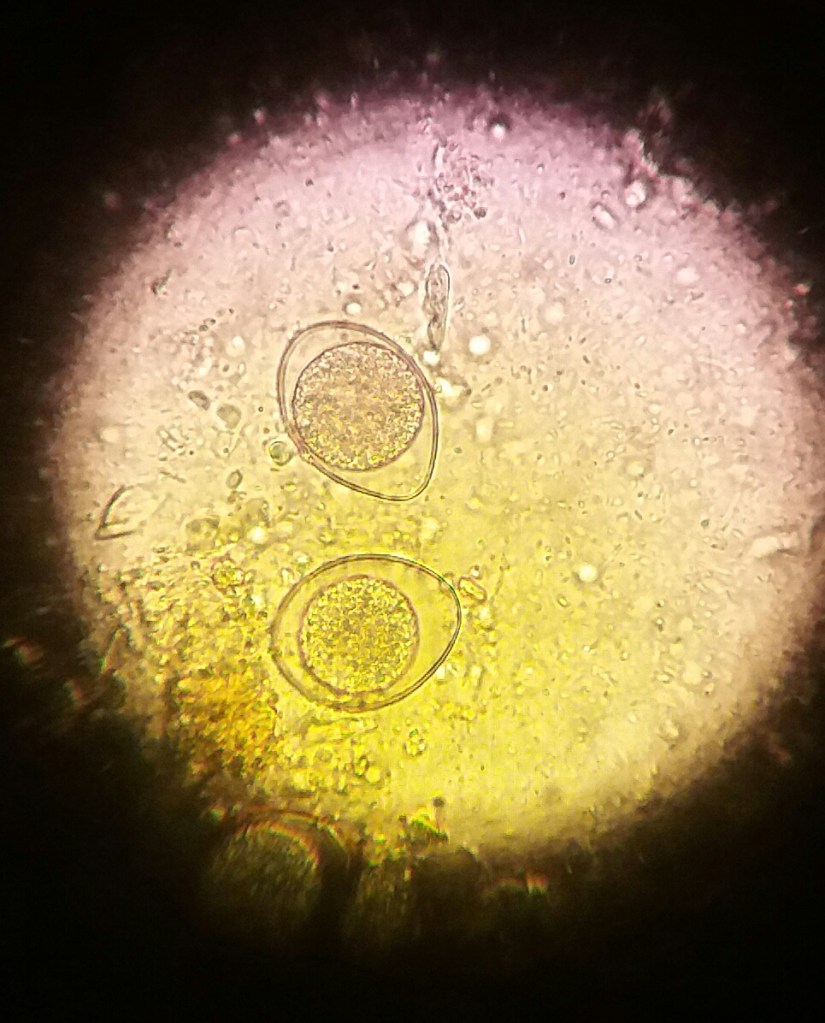

PARASITOLOGÍA FECAL